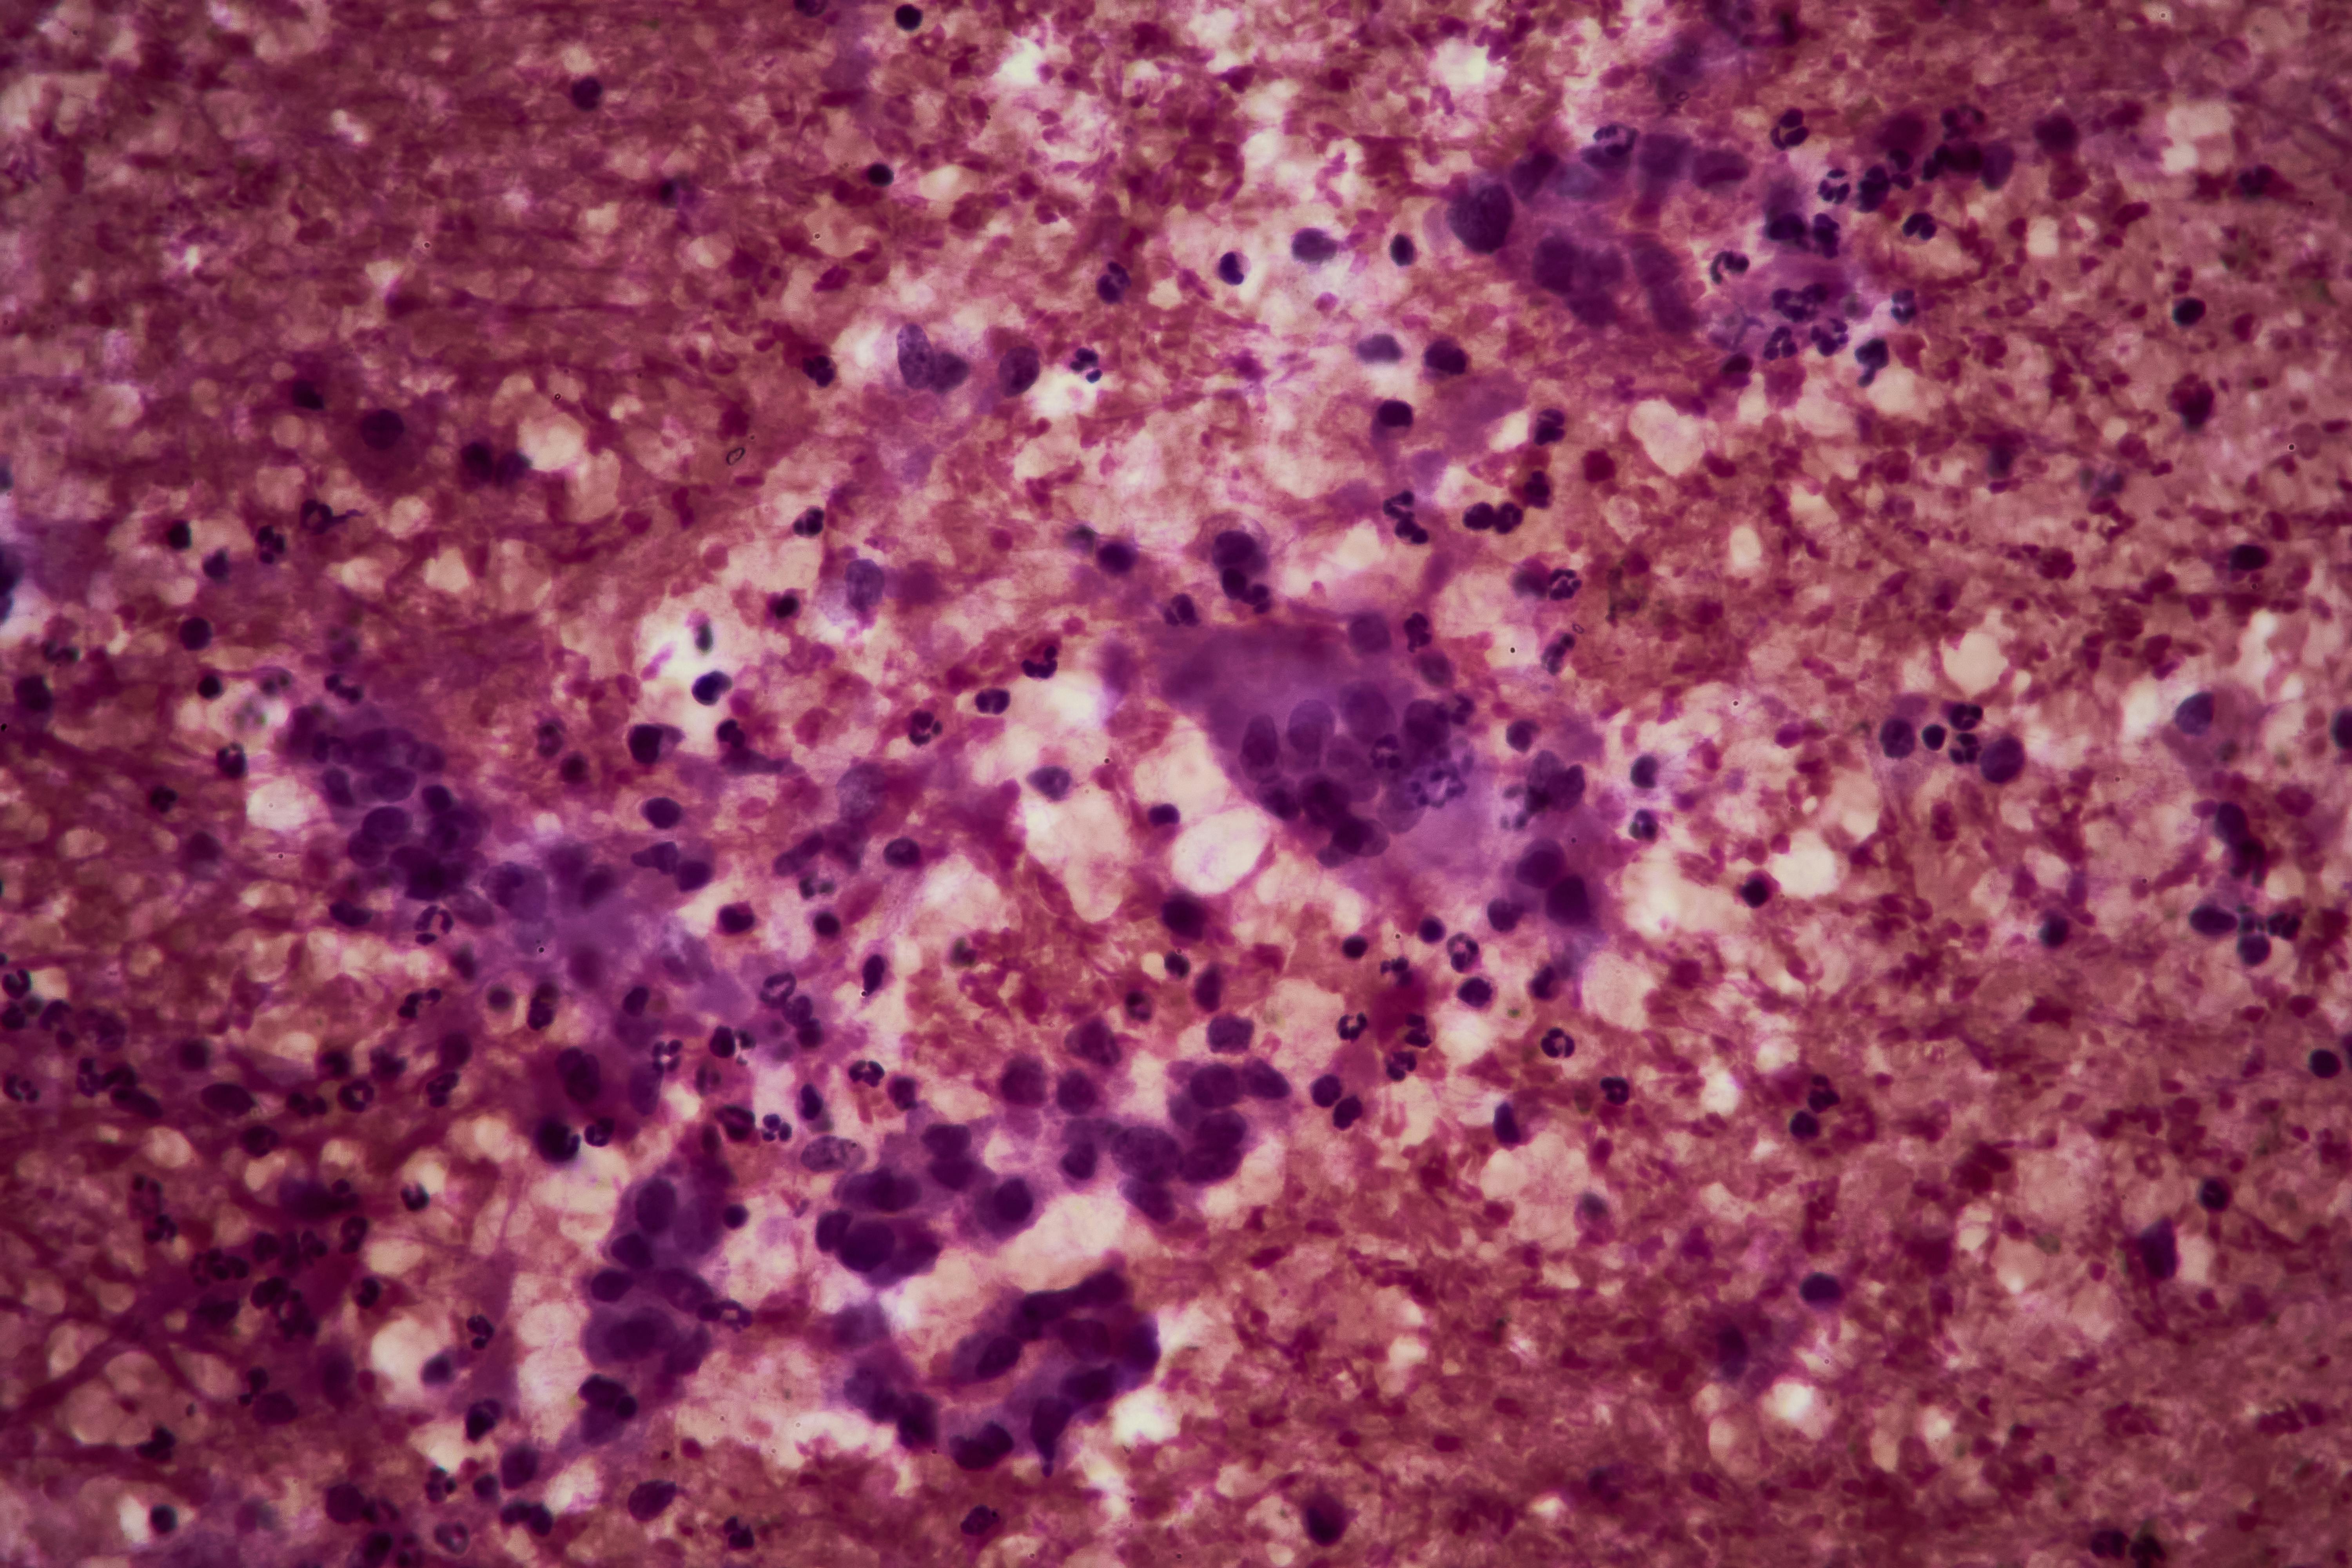

The test, developed by University of Pennsylvania Perelman School of Medicine, Philadelphia, and Mayo Clinic, Rochester, Minnesota researchers, fills a gap in pancreatic ductal adenocarcinoma screening as “there are no current screening methods to do so.” It merges aminopeptidase N (ANPEP) and polymeric immunoglobin receptor (PIGR) with CA19-9 and THBS2 to detect all stages of pancreatic cancer. Specifically, “91.9% of the time for all stages combined at a false positive rate of 5% in non-cases” and 87.5% for early-stage I and II.